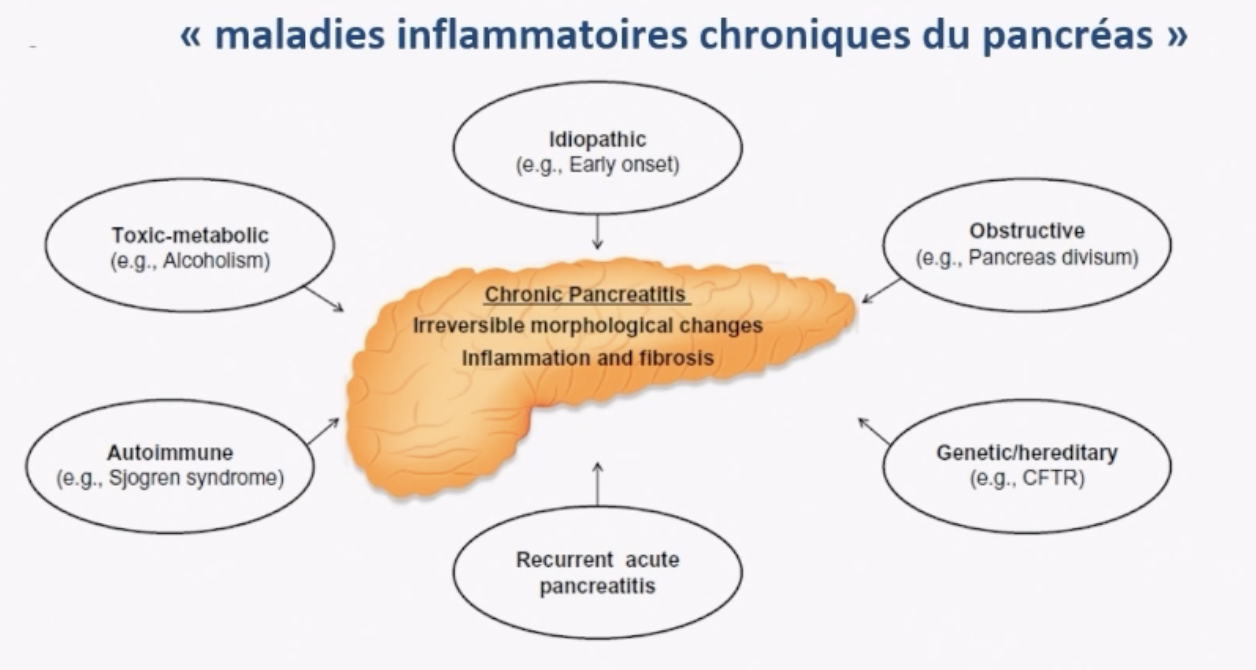

General

- Syndrome fibro-inflamamtoire comme reponse à des stress chroniques

- Essentiellement sur l’Alcool , favorisée par le Tabac

- Pour les plus jeunes patients, autres causes génétiques et malformatives